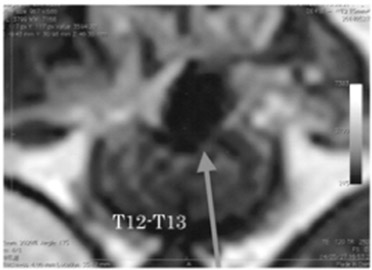

診察時も両後足完全麻痺で、深部痛覚が消失しており、グレード5の胸腰椎椎間板ヘルニアと診断しました。飼い主様とご相談して、まずMRI検査にて脊髄の状態を確認後、手術可能であれば手術を行うことで治療をすすめました。

胸椎12番目と13番目の椎間にて重度の椎間板逸脱が確認されました。また、脊髄を右側から重度に圧迫していたため、手術適応と判断し、片側椎弓切除手術を行い、圧迫している椎間板物質を摘出する手術を行いました。